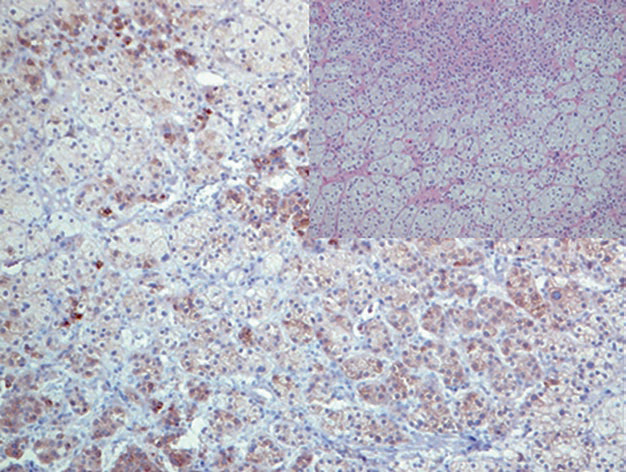

图5. 嗜铬细胞瘤,瘤细胞的胞核表达GATA-3。

图6. 肾上腺活检一例,神经母细胞瘤的细胞核表达GATA-3。